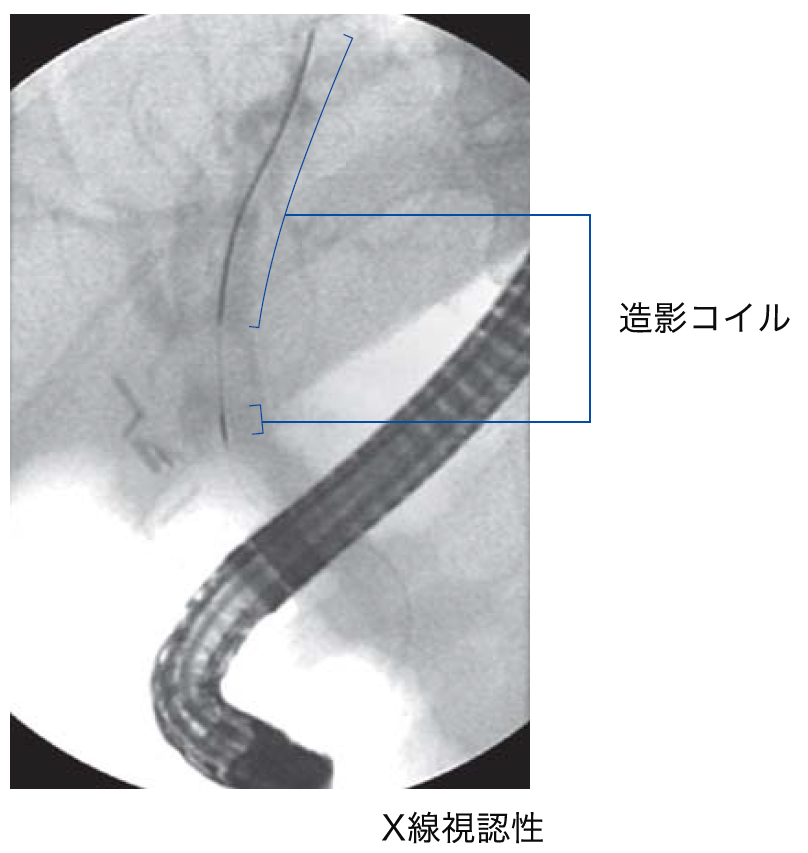

New Style Fluoroscopic Visibility

X線視認性の向上のために、先端部(先端から5cmまでと先端から7cmの部分)にX線不透過性の高い造影コイルを採用。さらに造影コイルを2分割する事で、細かな先端部の動きを確認し易くしています。